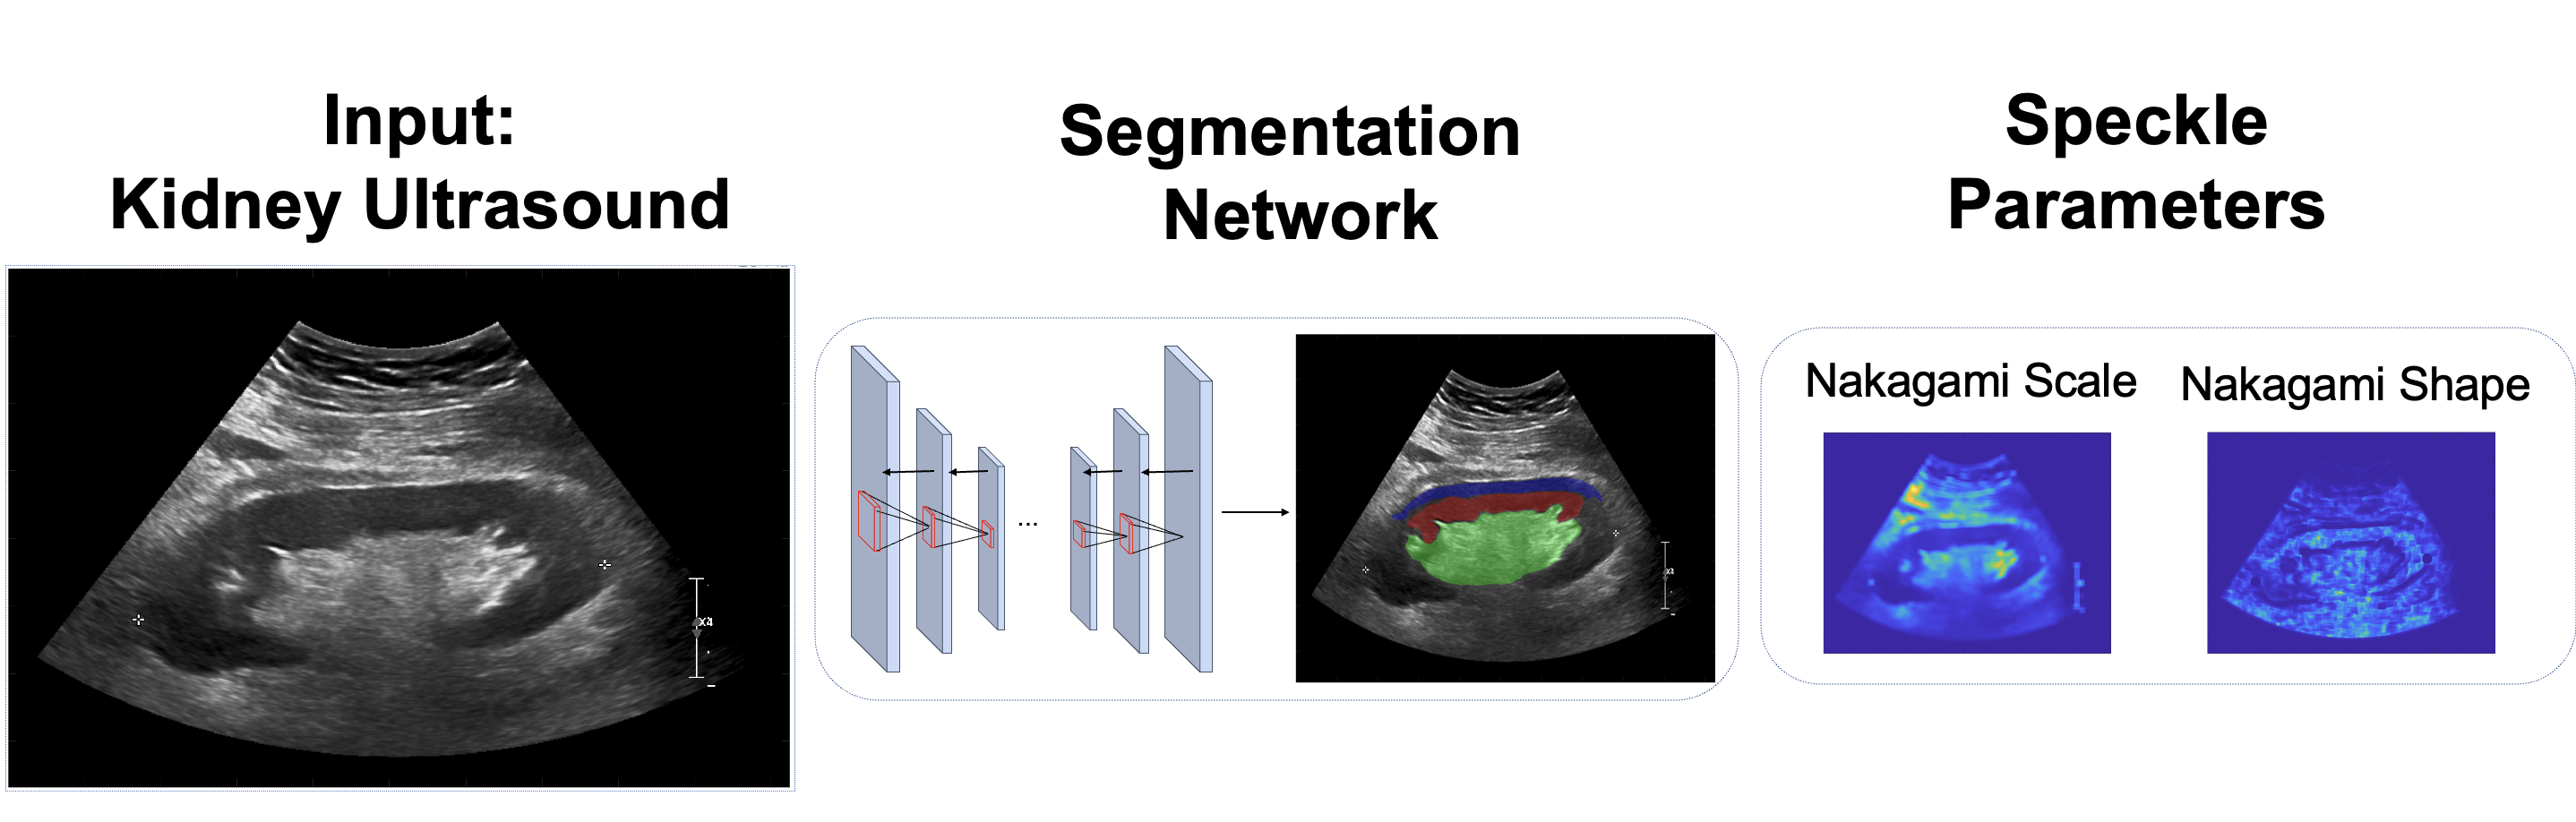

As an overview, each ultrasound image is automatically segmented into three regions of interest (cortex, medulla, and central echogenic complex) using a trained neural network. For each region of interest, seven different distributions are fit. Statistical analysis is performed to identify distributions whose parameters are significantly different across each region. For these identified distributions, goodness of fit and the relative entropy is evaluated. Finally, the results are stratified by different patient characteristics and, after data processing, are assessed for significant correlations with the distribution parameters.

- Figure 1:

-

Overview of key methods. For an input ultrasound image, the three regions of the kidney are extracted via a neural network. Seven different probability distributions are fitted onto each region, and statistical analysis is performed after fitting. The Nakagami distribution is one of the seven. Subsequent subgroup analysis is performed on patient factors to evaluate any differences.